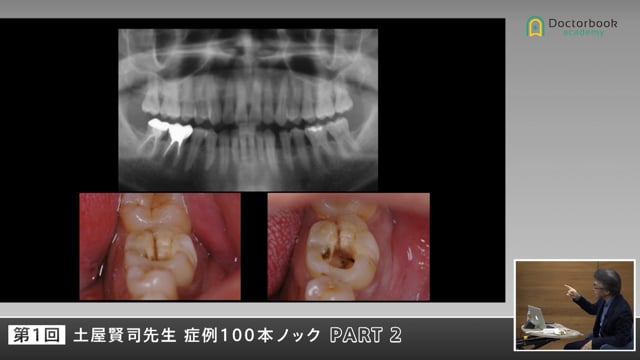

土屋先生が症例を通じ『どう考えて治療をするか』をテーマに卒業直後から卒後数年の若い歯科医師を対象にお話していただきます。

破折を主訴に来られた患者様に土屋先生はどのようにアプローチされるのでしょうか。患者様との信頼関係の重要性と長期予後のためのポイントをぜひご確認ください。再生する